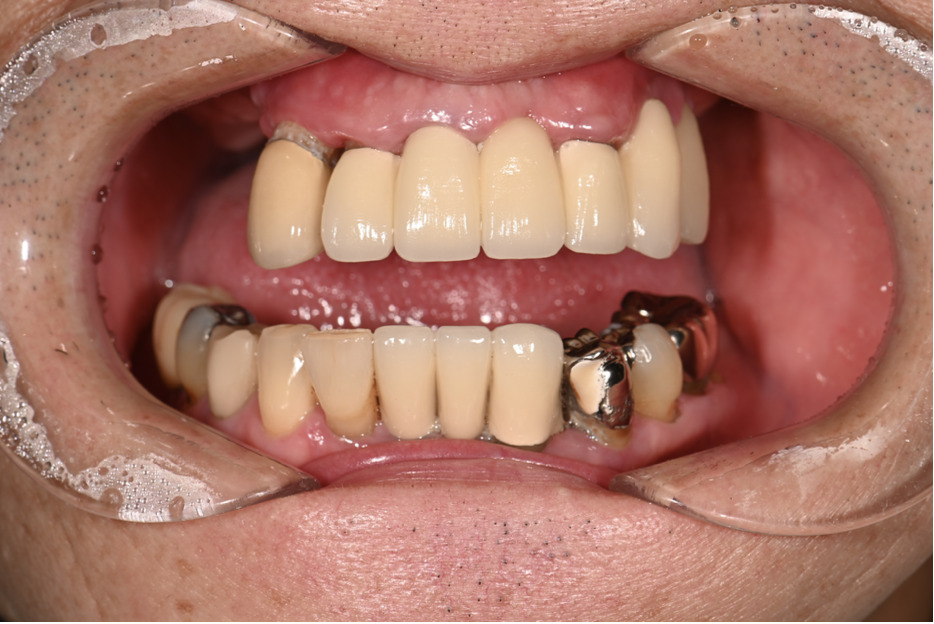

| 主訴 | 上の歯がぐらぐらする |

|---|---|

| 治療内容 | 上顎の歯が重度の歯周病のため全て抜歯し、

上顎に対するインプラント治療を行った。 午前中にインプラントの土台を入れ、夕方に上部構造(歯)を装着。 1日で噛めるようになる治療法。 |

| 治療期間 | 1日 |

| 治療費 | 250万円 |

| 治療 リスク | インプラント治療後2、3日はやや痛みを伴うことがあります。 |